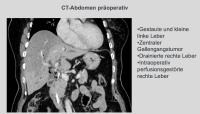

Im demonstrierten Fall handelt es sich um einen stenosierenden Gallengangstumor an der Hepatikusgabel Bismuth IIIb, der durch MRCP, ERCP und Bürstenzytologie diagnostiziert wurde.Eine erweiterte Rechtsresektion kam aufgrund der Atrophie des linken Leberlappens nicht in Frage. Deshalb wurde auf eine Entfernung der Lebersegmente 1,4,5 und 8 unter Erhalt der lateralen Segmente 6,7 und 2,3 zurückgegriffen, insbesondere da die Pfortadergabel und die linke Leberarterie bildmorphologisch nicht infiltriert erschienen.